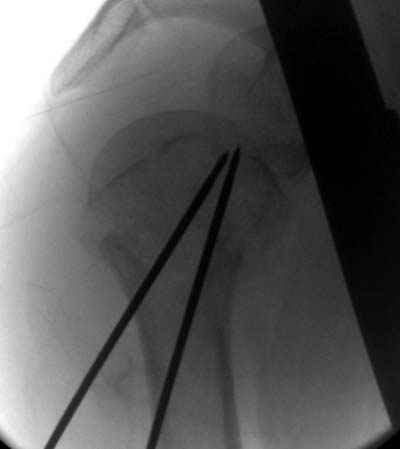

Здесь случай перелома-вывиха плеча, больному 56 лет, после "дважды" закрытой неудачной репозиции, опять же ургентно взяли в операционную, после полного общего обезболивания попытались сделать репозицию, и фиксацию провели спицами.

Больной находился в повязке, примерно напоминяющей косыночную, рекомендованы движения в локтевом суставе и маятниковые движения в плече, спицы удалены в три недели (были случаи миграции)